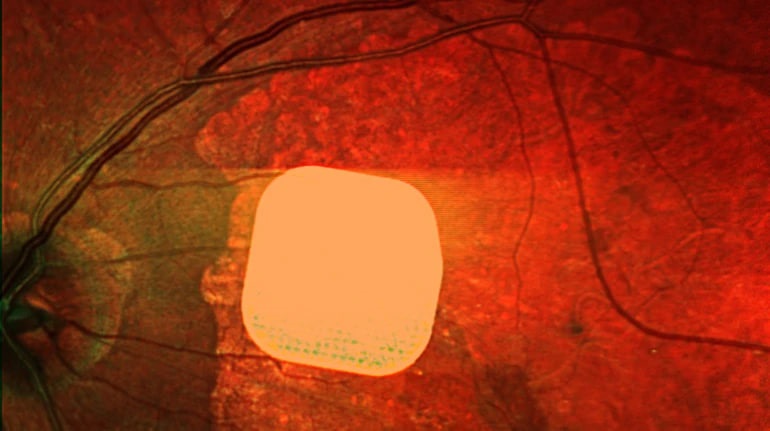

Технології - Британські лікарі частково повернули зір пацієнтам за допомогою мікрочипа

Технології

Британські лікарі частково повернули зір пацієнтам за допомогою мікрочипа

21.10.2025